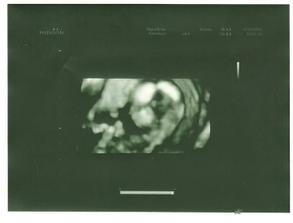

. 23.4.2010 Jsme měli poradnu. Pan doktor se na nás podíval dokonce 3D ultrazvukem a zjistil, že opravdu čekáme CHLAPEČKA. Bude se jmenovat Adámek. Dostali jsme krásnou fotečku. Krev i UTz jsou v pořádku a jsme zdraví.